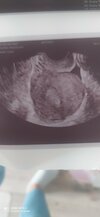

beta hcg ilościowo

Hej, czy wynik 0,05 13 dni po stosunku i 10 dni po owulacji jest wiarygodny i wyklucza ciążę? Beta zrobiona 4 dni przed spodziewana miesiączką

Załączniki

• IMG_20210828_100034.jpg

416,1 KB · Wyświetleń: 194